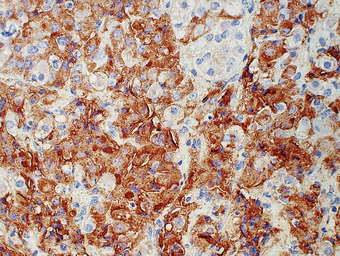

Phaeochromocytomas are brown, solid nodules, usually under 50 mm in diameter, often with areas of haemorrhagic necrosis (Fig. 17.9). Histologically, they consist of groups of polyhedral cells which give the chromaffin reaction, and are highly vascular (Fig. 17.10).

image

Fig. 17.9 Phaeochromocytoma. The adrenal medulla is expanded by a dark-coloured tumour with areas of degeneration and haemorrhage.

Fig. 17.10 Chromaffin cells in a phaeochromocytoma. There are groups of cells with granular cytoplasm, amidst which there are numerous branching capillaries.